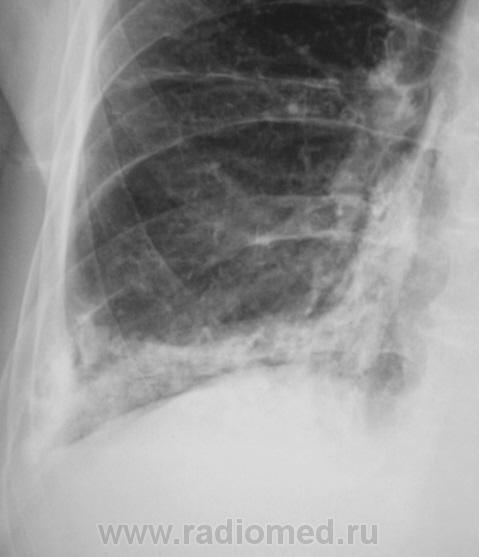

Пациент направлен на рентгенографию ОГК.

А томограмм нет. Просто демонстируется обызвествленная плевра.